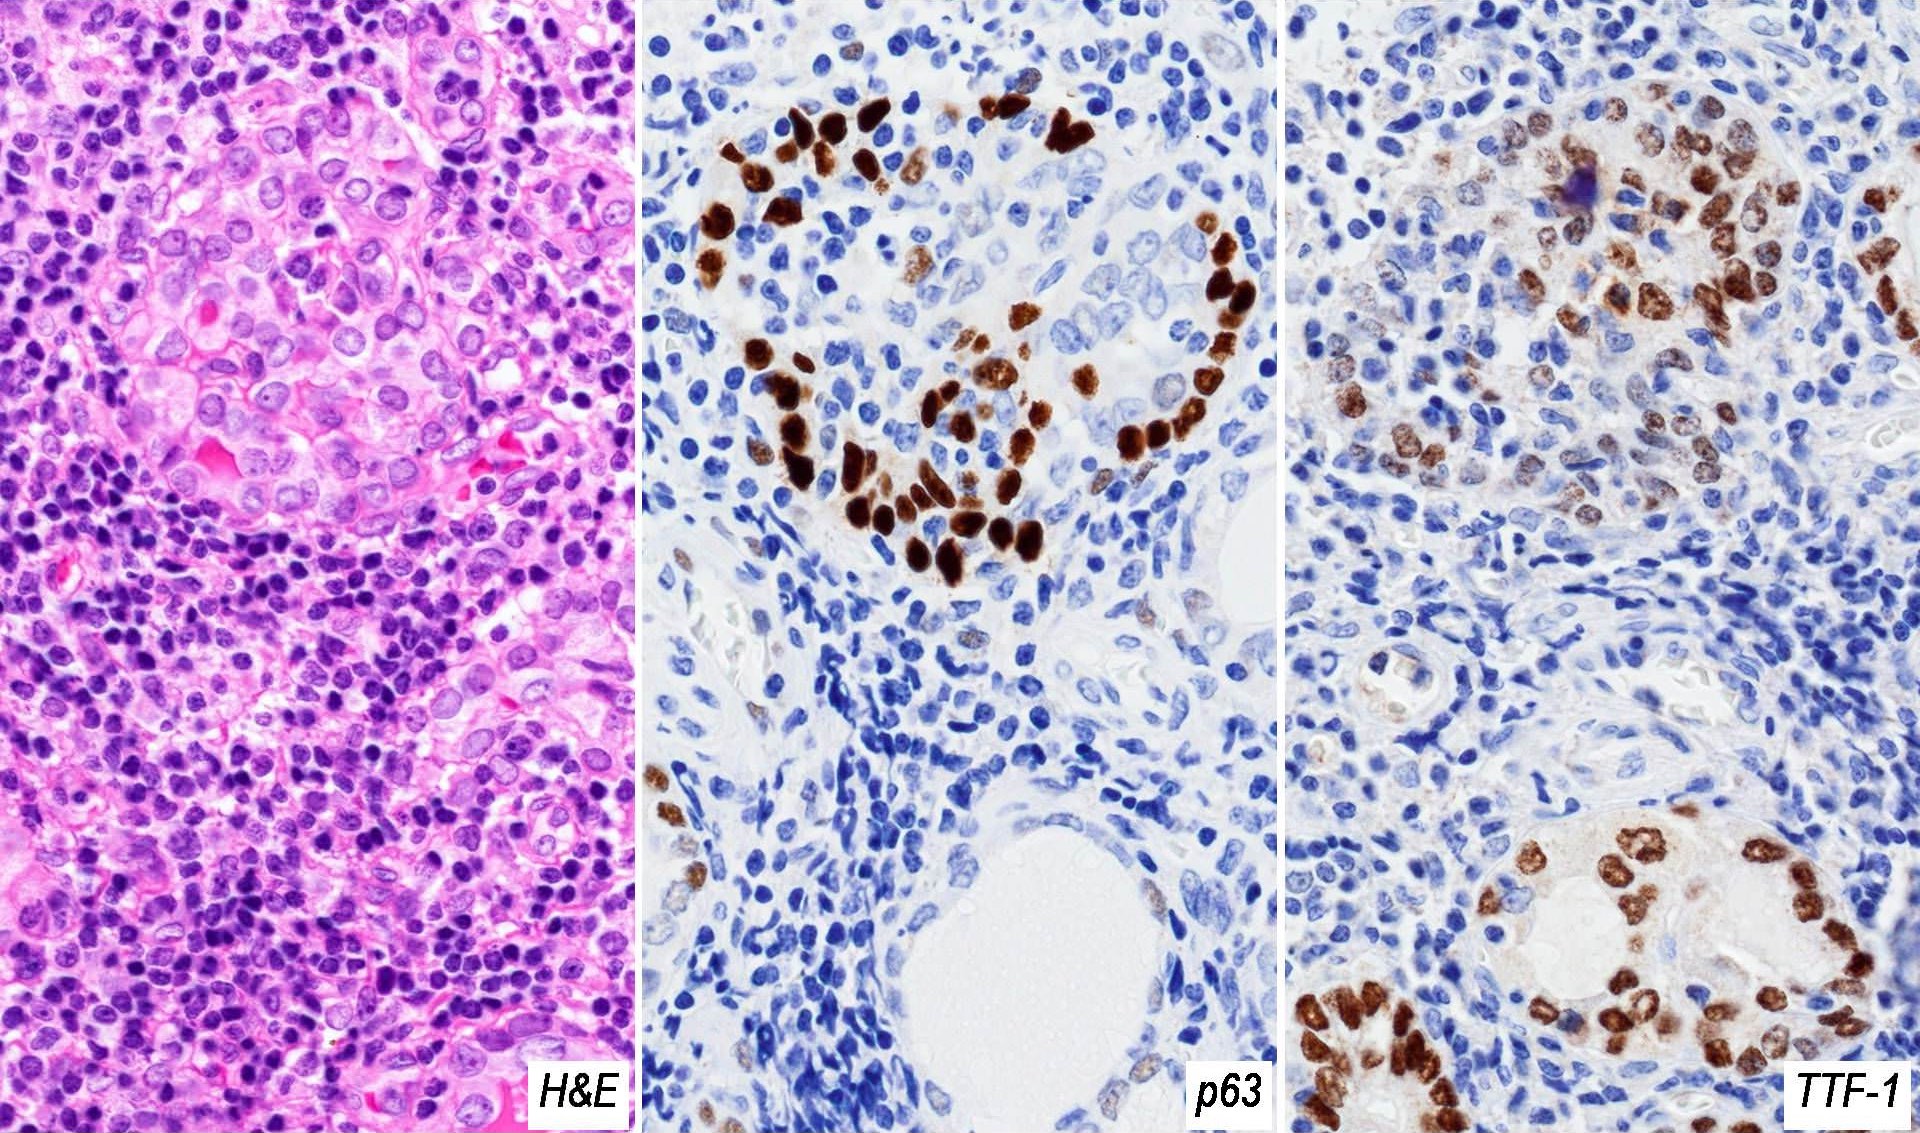

Microscopic (histologic) description

- Classic form: diffuse infiltration of thyroid parenchyma with lymphocytes and plasma cells; lymphoid follicle formation with germinal centers (Best Pract Res Clin Endocrinol Metab 2019;33:101367)

- Atrophic thyroid follicles; many lined by oncocytic cells / oncocytes having abundant granular eosinophilic cytoplasm; rarely squamous metaplasia

- Squamous metaplasia of follicular epithelium can be confused with solid cell nests (J Clin Endocrinol Metab 2012;97:2209)

Microscopic (histologic) images

Contributed by Andrey Bychkov, M.D., Ph.D. and Shipra Agarwal, M.D.

Positive stains

- High molecular weight keratin, p63 (Hum Pathol 2003;34:764)